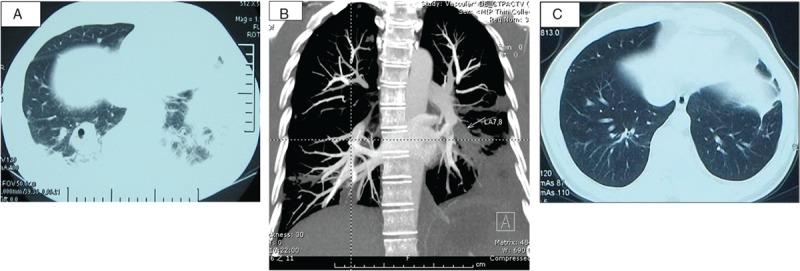

Based on the source of the embolus, septic pulmonary embolism (SPE) can be classified as cardiac, peripheral endogenous, or exogenous. Cardiac SPEs are the most common.We conducted a retrospective analysis of 20 patients with cardiac SPE hospitalized between 1991 and 2013 at a Chinese tertiary referral hospital.The study included 14 males and 6 females with a median age of 38.1 years. Fever (100%), cough (95%), hemoptysis (80%), pleuritic chest pain (80%), heart murmur (80%), and moist rales (75%) were common clinical manifestations. Most patients had a predisposing condition: congenital heart disease (8 patients) and an immunocompromised state (5 patients) were the most common. Staphylococcal (8 patients) and Streptococcal species (4 patients) were the most common causative pathogens. Parenchymal opacities, nodules, cavitations, and pleural effusions were the most common manifestations observed via computed tomography (CT). All patients exhibited significant abnormalities by echocardiography, including 15 patients with right-sided vegetations and 4 with double-sided vegetations. All patients received parenteral antimicrobial therapy as an initial treatment. Fourteen patients received cardiac surgery, and all survived.Among the 6 patients who did not undergo surgery, only 1 survived. Most patients in our cardiac SPE cohort had predisposing conditions. Although most exhibited typical clinical manifestations and radiography, they were nonspecific. For suspected cases of SPE, blood culture, echocardiography, and CT pulmonary angiography (CTPA) are important measures to confirm an early diagnosis. Vigorous early therapy, including appropriate antibiotic treatment and timely cardiac surgery to eradicate the infective source, is critical.